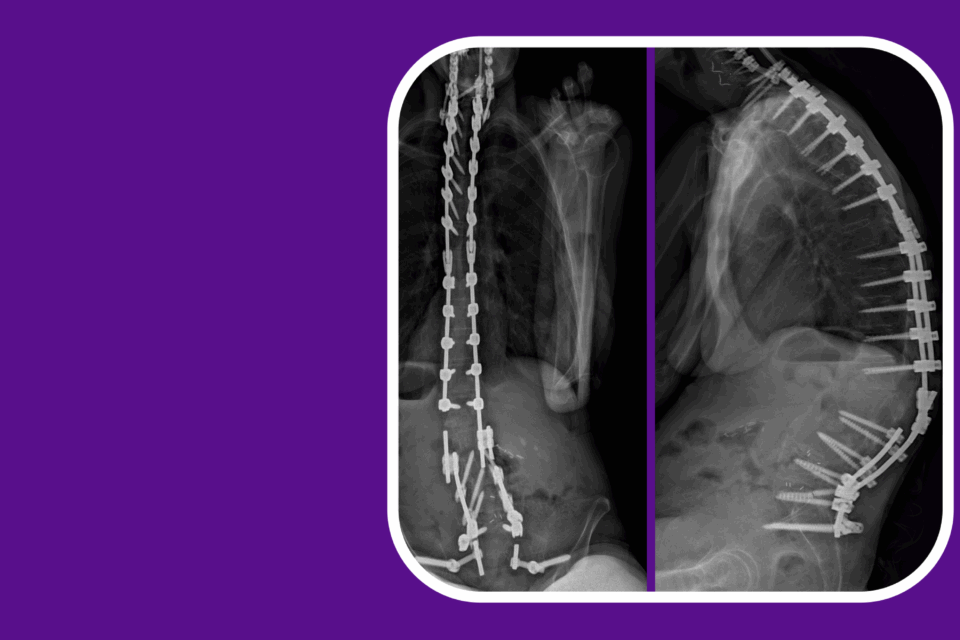

Surgeons Perform Novel Transorbital AVM Surgery